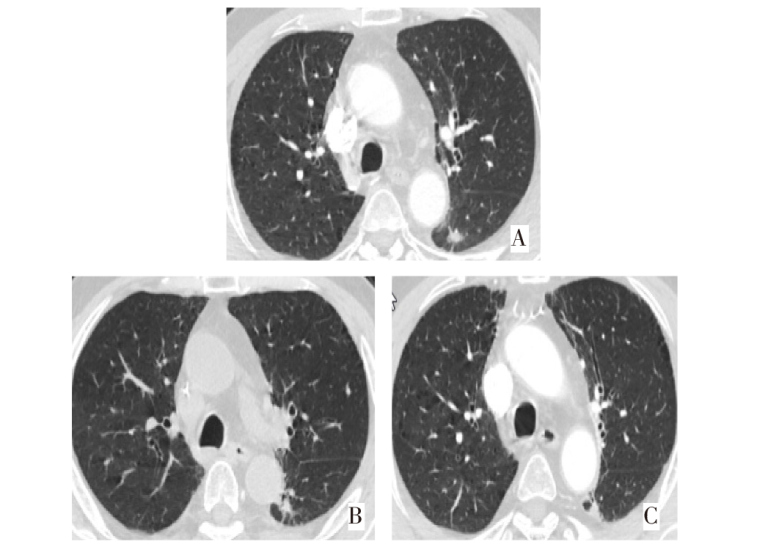

随着磁共振成像等影像学技术的不断发展,脑转移瘤的检出率越来越高。其中囊性脑转移发病率虽然远低于实性脑转移,但囊性脑转移瘤患者病情急,占位效应明显,是临床亟待解决的问题。既往文献报道囊性脑转移多见于乳腺癌和肺腺癌,特别是驱动基因阳性肺癌患者。该文报告1例以神经系统症状起病的小细胞肺癌囊性脑转移患者在多学科诊疗模式下获得临床治愈,在影像学动态评估以及微小残留病灶检测下避免过度治疗,延长生存期的基础上获得较高的生活质量。

With the continuous development of imaging techniques such as magnetic resonance imaging, the detection rate of brain metastases is increasing. Although the incidence rate of cystic brain metastasis is far lower than that of solid brain metastasis, patients with cystic brain metastasis are in urgent condition and have obvious space occupying effect, which is an urgent clinical problem. Previous literature has reported that cystic brain metastasis is more common in breast cancer and lung adenocarcinoma, especially in lung cancer patients with positive driver gene. This article reports a case of small cell lung cancer with cystic brain metastasis, which started with neurological symptoms, and was clinically cured under a multidisciplinary diagnosis and treatment model. Through dynamic imaging evaluation and molecular residual lesion detection, the patient can avoid overtreatment and achieved a relatively higher quality of life on the basis of prolonging survival.